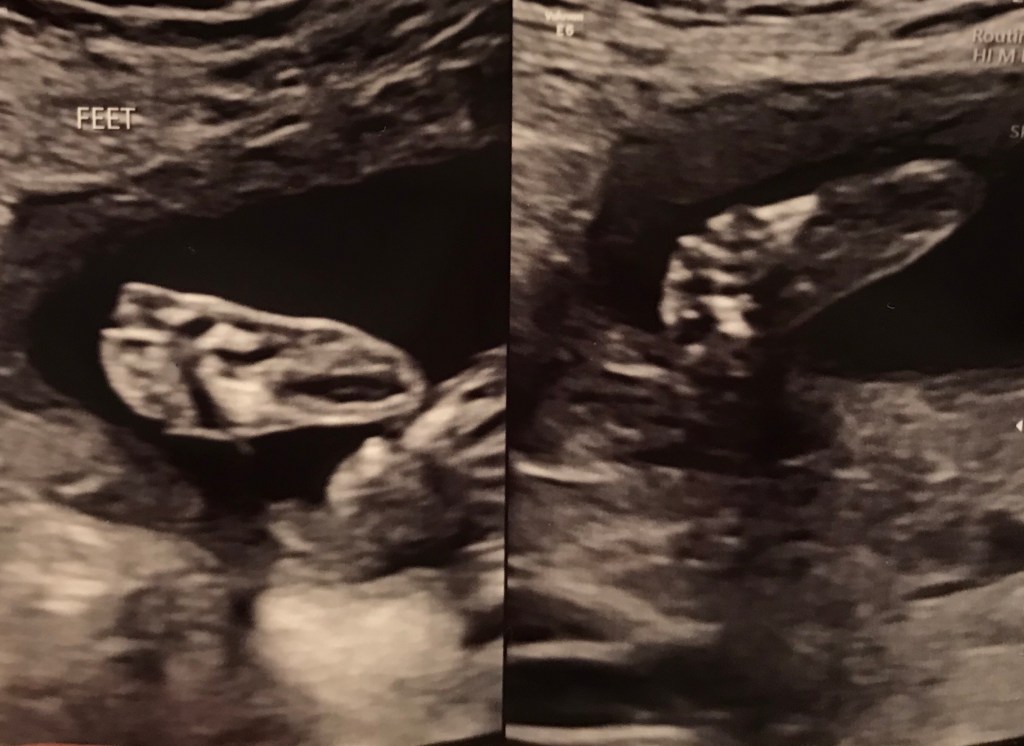

The end of this year and Christmas brings us to the due date of our last loss- Lane. He was going to be a Christmas baby and I thought our little miracle.

I wasn’t sure where my heart would be at this end of year. Today is his due date- December 23, 2025. And while my arms don’t hold him- my heart always will. He is whole with Jesus. Lane had an anomaly that wouldn’t have allowed him to survive much past birth. And while he is not an angel, little Lane was created for far greater purposes- he is part of eternal plans that I can’t yet know.

This month I have contemplated on his name and the names of our others- Our first little Sparrow, who flew away, our second- Orion was always meant for the heavens. I too sought to fly away from the heaviness of those losses and press ahead. Then Lane. That loss was bewildering. Lane grounded me. He was named after the road God has asked us to travel, or rather put us on. I have slowly come to settle into this lane, this reality that loss doesn’t always hold a beautiful ending or a bow on it like a Christmas present should.